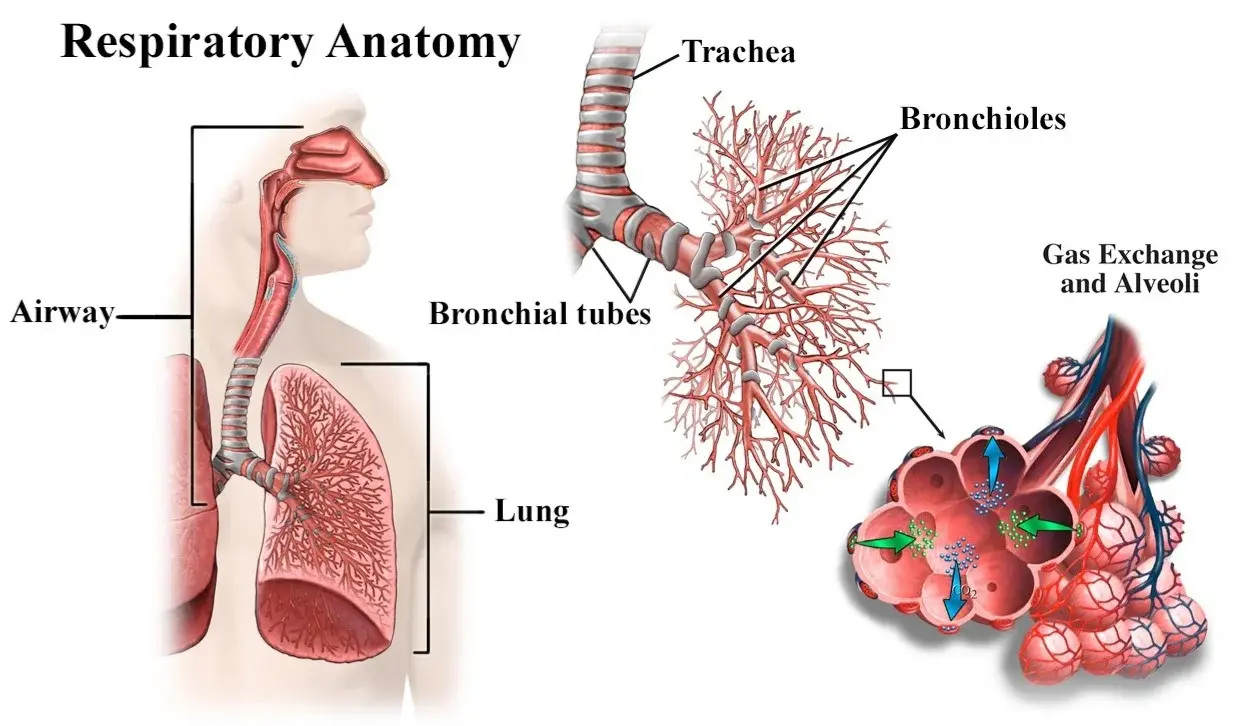

Routine tests miss the "respiratory evil" that Dr. Carson identifies in his functional medicine practice: A dense, hardened layer of old mucus and toxins (PM2.5, tar, heavy metals) that glues the air sacs (alveoli) shut.

"Inhalers only force the airways open for a few hours," Dr. Carson explains. "But in COPD patients, the Suffocation Layer is so thick that oxygen can't penetrate. It's like trying to breathe through a wet sponge coated in asphalt. This is why standard treatments fail."

Ben Carson:"The turning point in perfecting Healvora was introducing Recombinant Collagen Peptides. This acts as a 'biological scaffolding' for alveolar repair. Combined with Wildcrafted Mullein and Dendrobium, we aim to rebuild lost lung elasticity instead of just suppressing a cough."